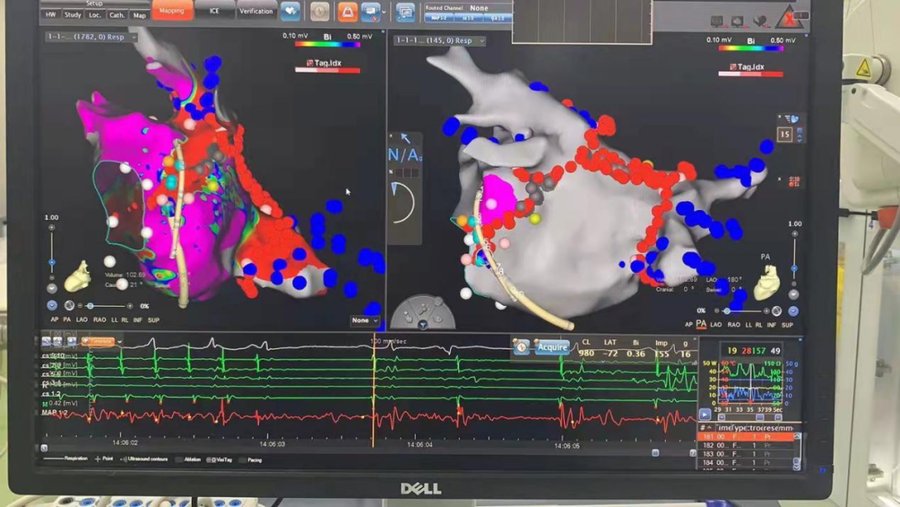

该患者治疗中首先利用CARTO三维成像重建左房并行激动标测,左右心房心内膜标测未标测到心动过速全周长,考虑心外膜Marshall静脉可能参与房扑的激动及维持。Marshall静脉因其特殊解剖特点,经心内膜途径的导管消融难度极高,且长时间的持续消融又会增加心包填塞等手术风险。因此,Marshall 静脉无水乙醇化学消融可能是该患者目前最为可行的治疗方案。

按照手术流程,经下腔静脉将造影导管送至冠状窦内造影见Marshall 静脉显影,沿导丝将球囊送入Marshall静脉内,扩张封堵后经中心腔将2ml无水乙醇缓慢注Marshall 静脉内,输注20秒后患者即恢复窦性心律,操作过程中患者未述明显不适,无水酒精消融过程总共耗时15分钟。术后验证二尖瓣峡部彻底阻滞,未再诱发出任何性质的心律失常。